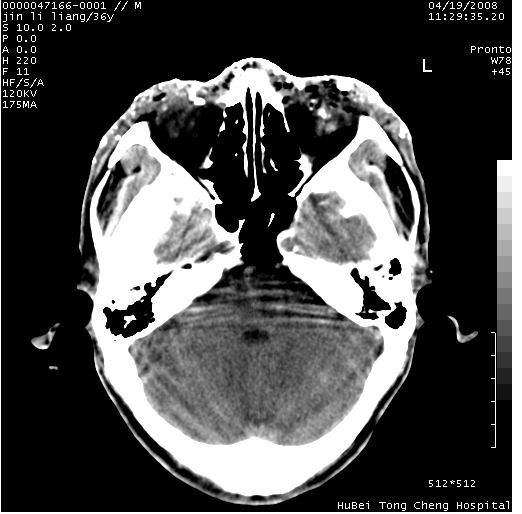

患者 男,36岁。头面部“土炮”炸伤。pe:面目全非,伤口流血不止。

临床诊断:头面部外伤。

颅脑ct轴位平扫(层厚、层距均为10mm),图像如下:

左眼球破裂,异物.

左眼球破裂,球内异物

左眼球内容物浑浊其内见气体影,头面部异物.

左眼球破裂并异物,眶周、额顶部头皮及软组织挫伤并异物

迎面一炮,满脸开曝。额顶部头皮及软组织挫伤并异物,左眼球破裂积气并异物,典型的面目全非,惨不忍睹。

左眼球破裂积气并异物,眶周、额顶部头皮及软组织挫伤并异物,右侧眼环前内分异物

1左侧眼球破裂并积气,球内、框内异物。

2额部顶部软组织伤。